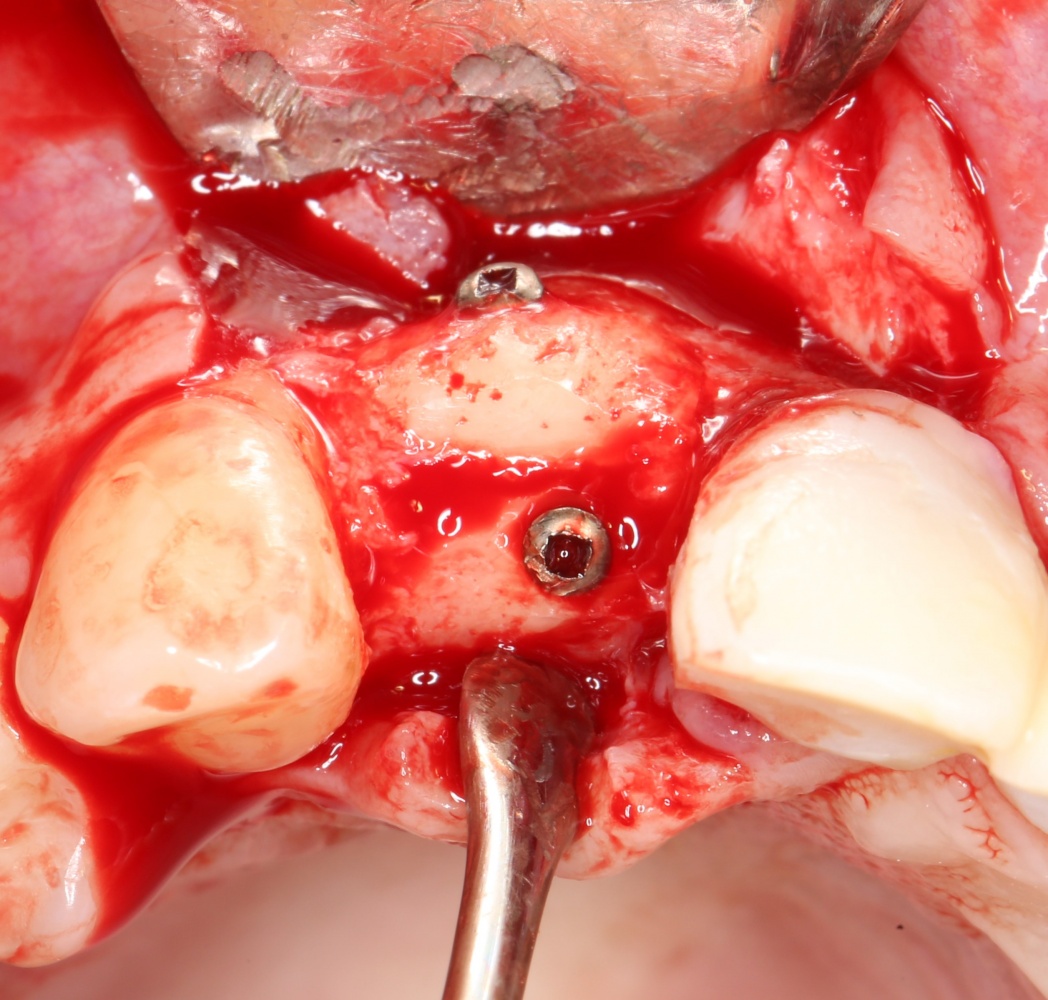

Установка имплантатов.

Напомню, что для этой работы я выбрал субкрестальные имплантаты Ankylos C/X. Они прекрасно сочетаются с любым методом остеопластики.

Я не планирую установку супраструктур или коронок, поэтому на уровень первичной стабильности можно положить болт. Даже наоборот — чем меньше крутящий момент при установке, тем лучше. Для имплантатов Ankylos и подобных им, это особенно важно. В общем, момент силы при установке — не более 10-15 Нсм.

Ремарка: имплантаты с предустановленными имплантодержателями хороши тем, что с ними легко контролировать позиционирование имплантатов. В случае с Ankylos С/Х - еще и крутящий момент. Имплантодержатель должен отсоединяться от имплантата с легким щелчком. Если его клинит, и тебе приходится прикладывать для этого усилия, то ты, однозначно, превысил момент силы во время установки имплантата. Следовательно, жди проблем.

Глянем на то, что получилось: